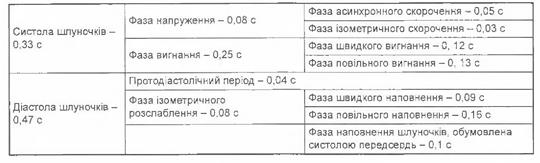

Фази серцевого циклу

Фази серцевого циклу